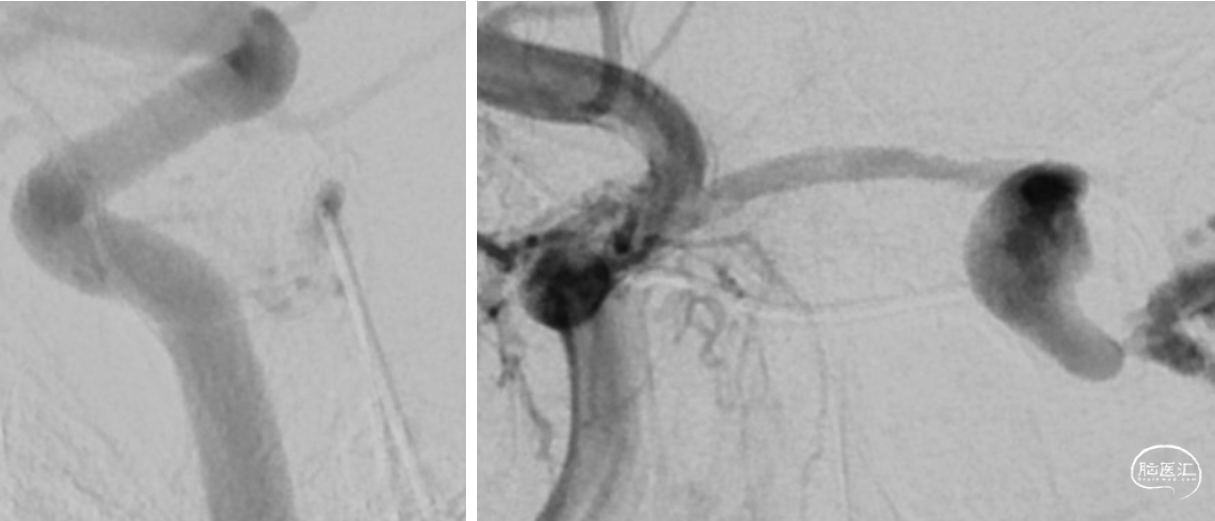

手术经过 R-ICA

动静脉分别建立路径

动静脉同时造影

微导管超选

微导管超选造影

第二次栓塞治疗

手术方案:静脉入路左侧海绵窦区硬脑膜动静脉瘘引流开通并栓塞术

手术难点:开通正常静脉与DAVF引流静脉的间隔

器械耗材:微导丝(PT / PILOT50 / 150)、微导管、ONYX-18等

泥鳅导丝尝试开通

微导丝微导管尝试开通

微导丝微导管反复尝试开通

微导丝微导管尝试开通

微导丝微导管尝试开通 跨海绵间窦仍无法进入

微导丝微导管盘绕引流间隙1周

双侧ICA造影见DAVF消失